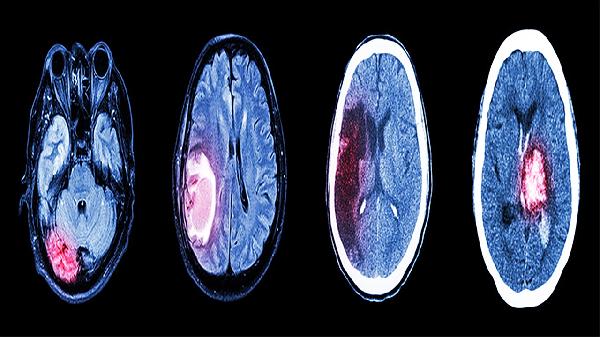

闭合性颅脑损伤轻型严重吗

闭合性颅脑损伤轻型通常不严重,属于颅脑损伤中最轻微的类型,主要表现为短暂意识障碍、头痛头晕等症状,多数患者经休息和观察后可完全恢复。具体表现与处理方式主要有脑震荡、头皮血肿、短暂性脑功能障碍、心理调适